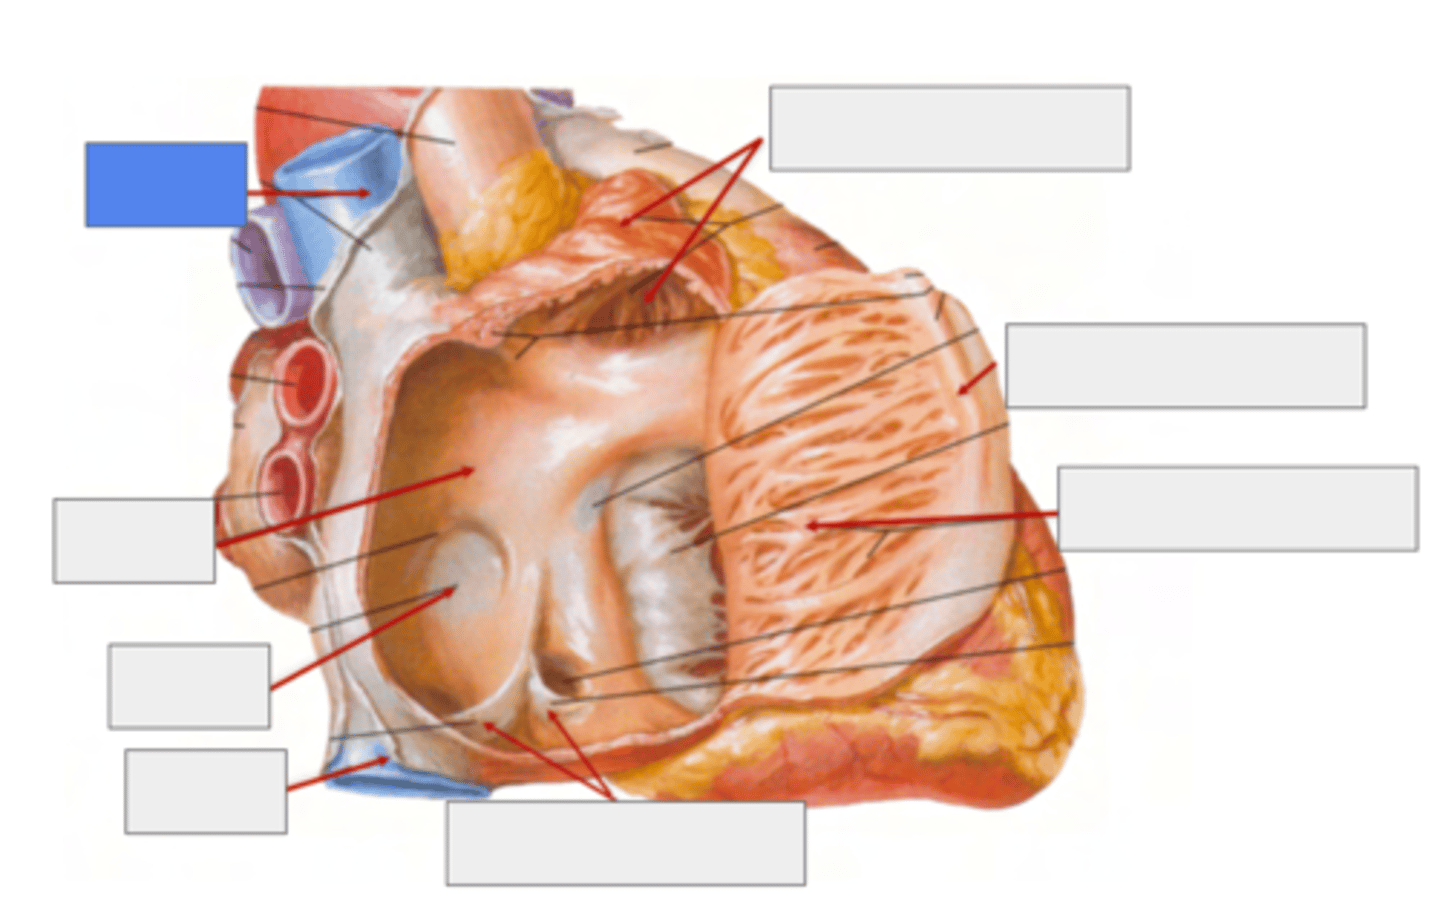

What are the six surfaces that form the internal structure of the right atrium?

. superior

. inferior

. posterior

. medial

. anterior

. lateral walls.

What is the vein entering without valve in the right atrium?

Superior Cava vein

(No valve for entry)

What are the veins entering with valves in the right atrium?

Inferior cava vein (left)

Coronary sinus (right)

Both of them with a valve for entry

What is pointing the blue square?

valves of inferior vena cava and coronary sinus

What is the trabeculated wall in the atrium?

Right Auricle

What are the name of the musculi of the right auricle?

Musculi pectinati

TRABECULATED WALL VS THE SMOOTH INTERIOR PART OF THE ATRIA

What separates the trabeculated from the smooth walls in the atrium?

Crista terminallis

ANATOMICAL LANDMARK indicates the transition between the original embryological parts of the atrium.

What is the remnant of the foramen ovale?

Fossa Ovalis

belongs to the Septum Primum (thinner atrium region)

during fetal live it serves as a passage of blood from let to right